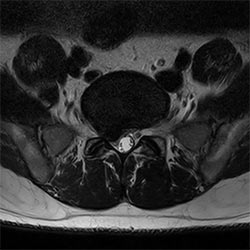

Spine